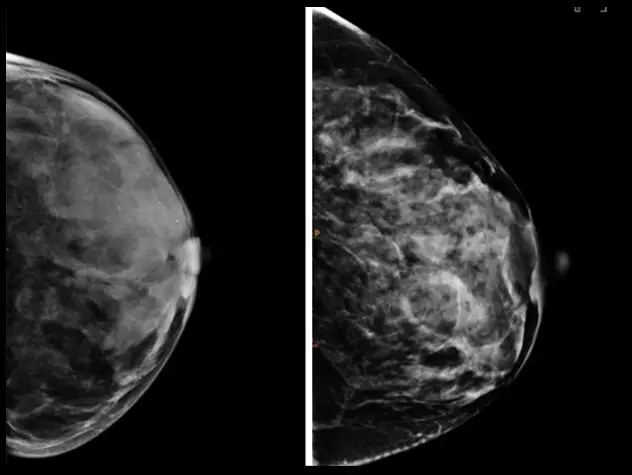

NewYork-Presbyterian cancer specialists are at the forefront of expanding and innovating treatment for everything from breast cancer to glioblastoma. In 2025, our physicians and researchers from Columbia and Weill Cornell Medicine improved progression-free survival for multiple types of cancer, employed artificial intelligence to inform clinical care, discovered biomarkers that predict treatment responses to help personalize care in complex cases, and more. These advancements are breaking ground for new solutions that can improve cancer outcomes for all patients.

Through two world-class cancer centers – Columbia’s NCI-designated Herbert Irving Comprehensive Cancer Center and Weill Cornell Medicine’s Meyer Cancer Center, our team of physician-scientists are transforming care for cancer patients across a broad spectrum of malignant diseases and conditions. From pursuing novel laboratory research to better predict, diagnose and treat cancer, to conducting clinical trials of promising new therapies, our physicians provide personalized treatment plans to deliver optimal outcomes.